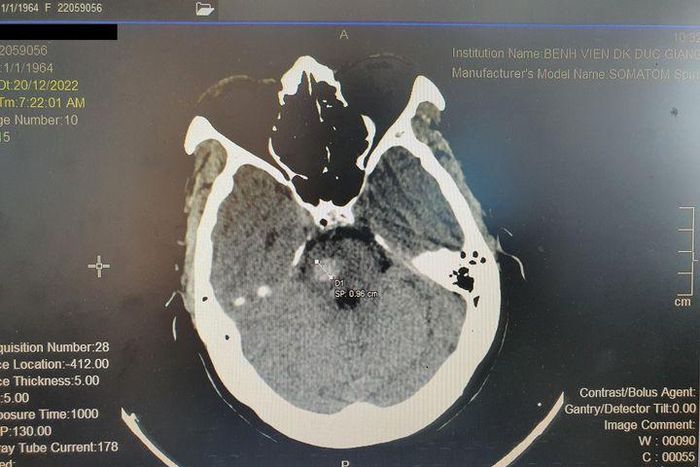

Bệnh nhân ngay lập tức được các bác sĩ đánh giá và chụp phim cắt lớp sọ não, chẩn đoán nhanh chóng được đưa ra là xuất huyết cầu não. Bệnh nhân T. ngay lập tức được chuyển đến đơn nguyên điều trị đột quỵ để tiến hành các can thiệp cần thiết.

Hình ảnh chụp phim não của bệnh nhân T. Ảnh BVCC

BS. Đinh Thế Tiến, Khoa Nội tổng hợp, Bệnh viện Đa khoa Đức Giang cho biết, bệnh nhân T. là trường hợp đột quỵ não xuất hiện rất bất ngờ, cần được nhanh chóng phát hiện và xử trí.